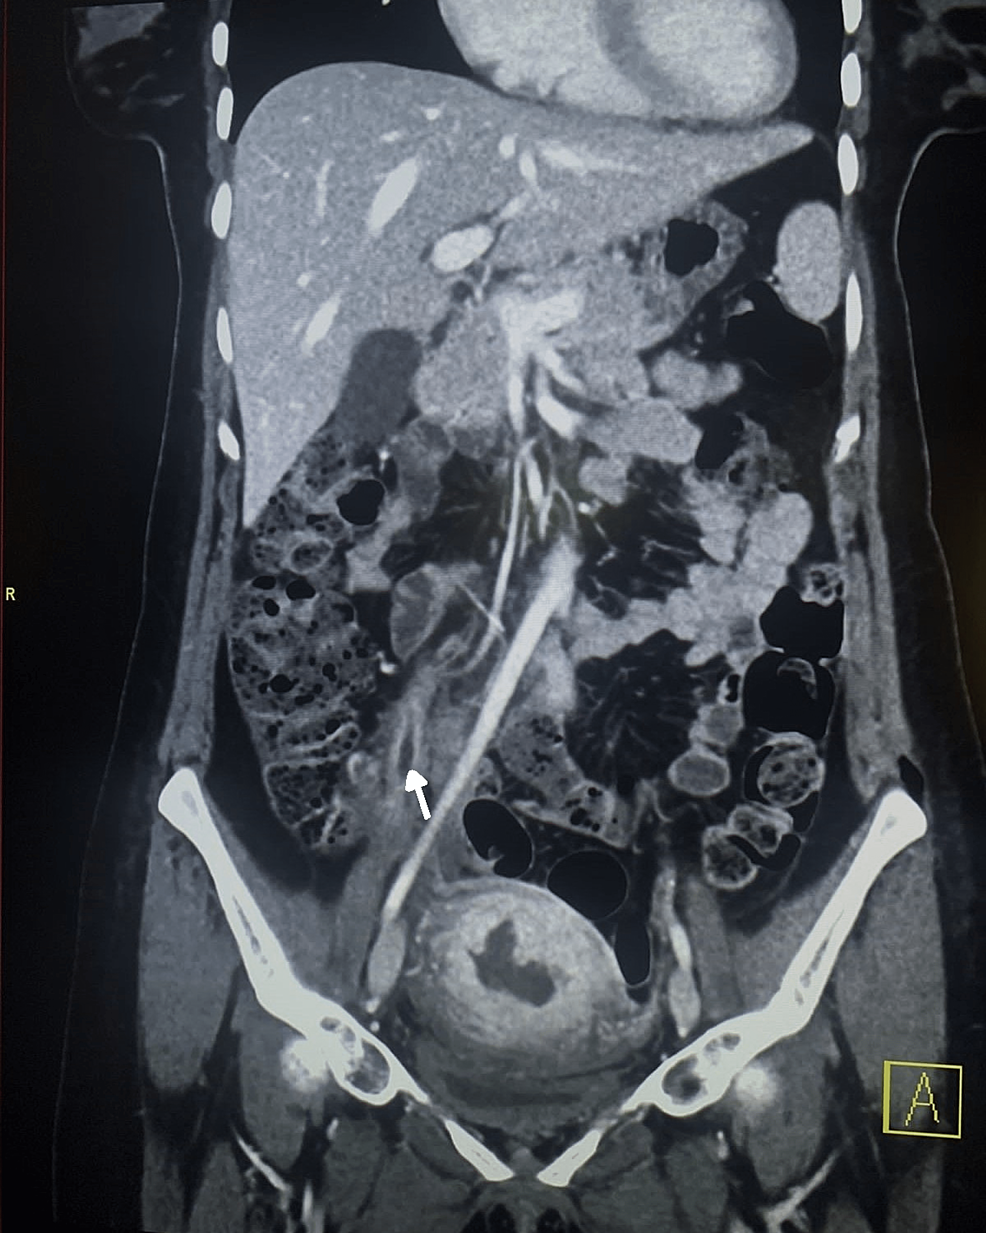

Septic thrombophlebitis of the portal vein (pylephlebitis) diagnosis Septic Thrombophlebitis Treatment Uptodate Septic thrombophlebitis is a clinical syndrome resulting from an infectious source at the. septic pelvic thrombophlebitis (spt) can occur in the setting of pelvic vein endothelial damage, venous stasis, and. septic thrombophlebitis, as a result of invasion from adjacent nonvascular infections, includes conditions such as. thrombosis involving the deep veins of the upper extremity (axillary, brachial) or. Septic Thrombophlebitis Treatment Uptodate.